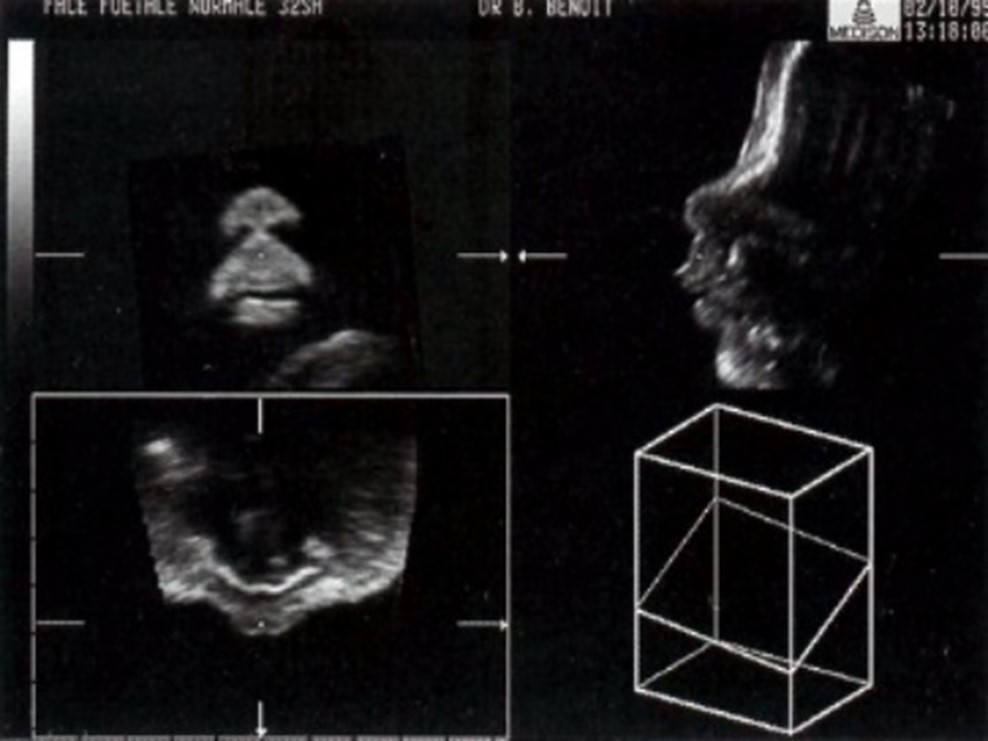

Принципы формирования изображения аналогичны тем, что используются в стандартном 2D-сканировании. Датчик отправляет короткие импульсы звуковых волн к тканям пациента и фиксирует отраженные сигналы. Собранные данные обрабатываются с помощью специального программного обеспечения и отображаются на экране в виде пикселей или точек с различной яркостью. В то время как двухмерный метод создает плоскостные сечения, трехмерная технология формирует изображение в трех ортогональных плоскостях, позволяя одновременно визуализировать горизонтальные, поперечные и продольные срезы.

Какова разница между 3D и 4D УЗИ? Обе объемные технологии позволяют специалистам детально изучить анатомические взаимосвязи между органами, визуализировать объекты в горизонтальной плоскости и исследовать интересующую область под любым углом в пределах просканированного объема.

Однако изображение, получаемое при 3D, является статичным. В отличие от него, 4D предоставляет объемное изображение в режиме реального времени, что позволяет сонографисту наблюдать за движениями различных частей тела плода и его мимикой.

Объемное ультразвуковое исследование предоставляет детализированные анатомические изображения, которые недоступны при стандартном 2D-сканировании. Эта методика позволяет более точно установить эмбриональный возраст на ранних сроках беременности, а также своевременно обнаруживать аномалии развития сердца, лица, конечностей, головного мозга и позвоночника, обеспечивая высокую точность измерений исследуемых объектов.